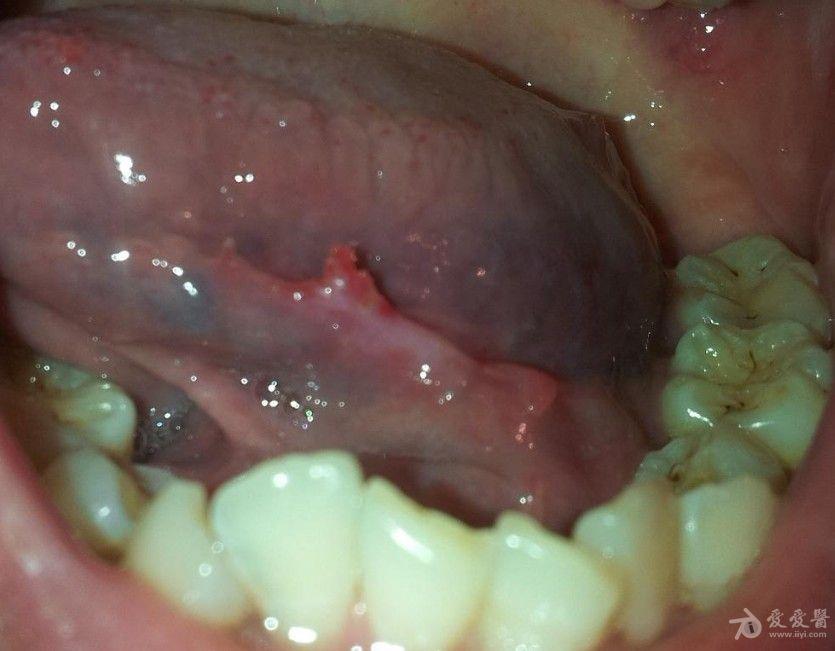

女性口腔尖锐湿疹初期图片_口腔尖锐湿疣_鬼臼毒素软膏治口腔湿疣

口腔尖锐湿疣,多位于舌下系带处,舌两侧,咽喉处,咽喉处疣体较大的时候